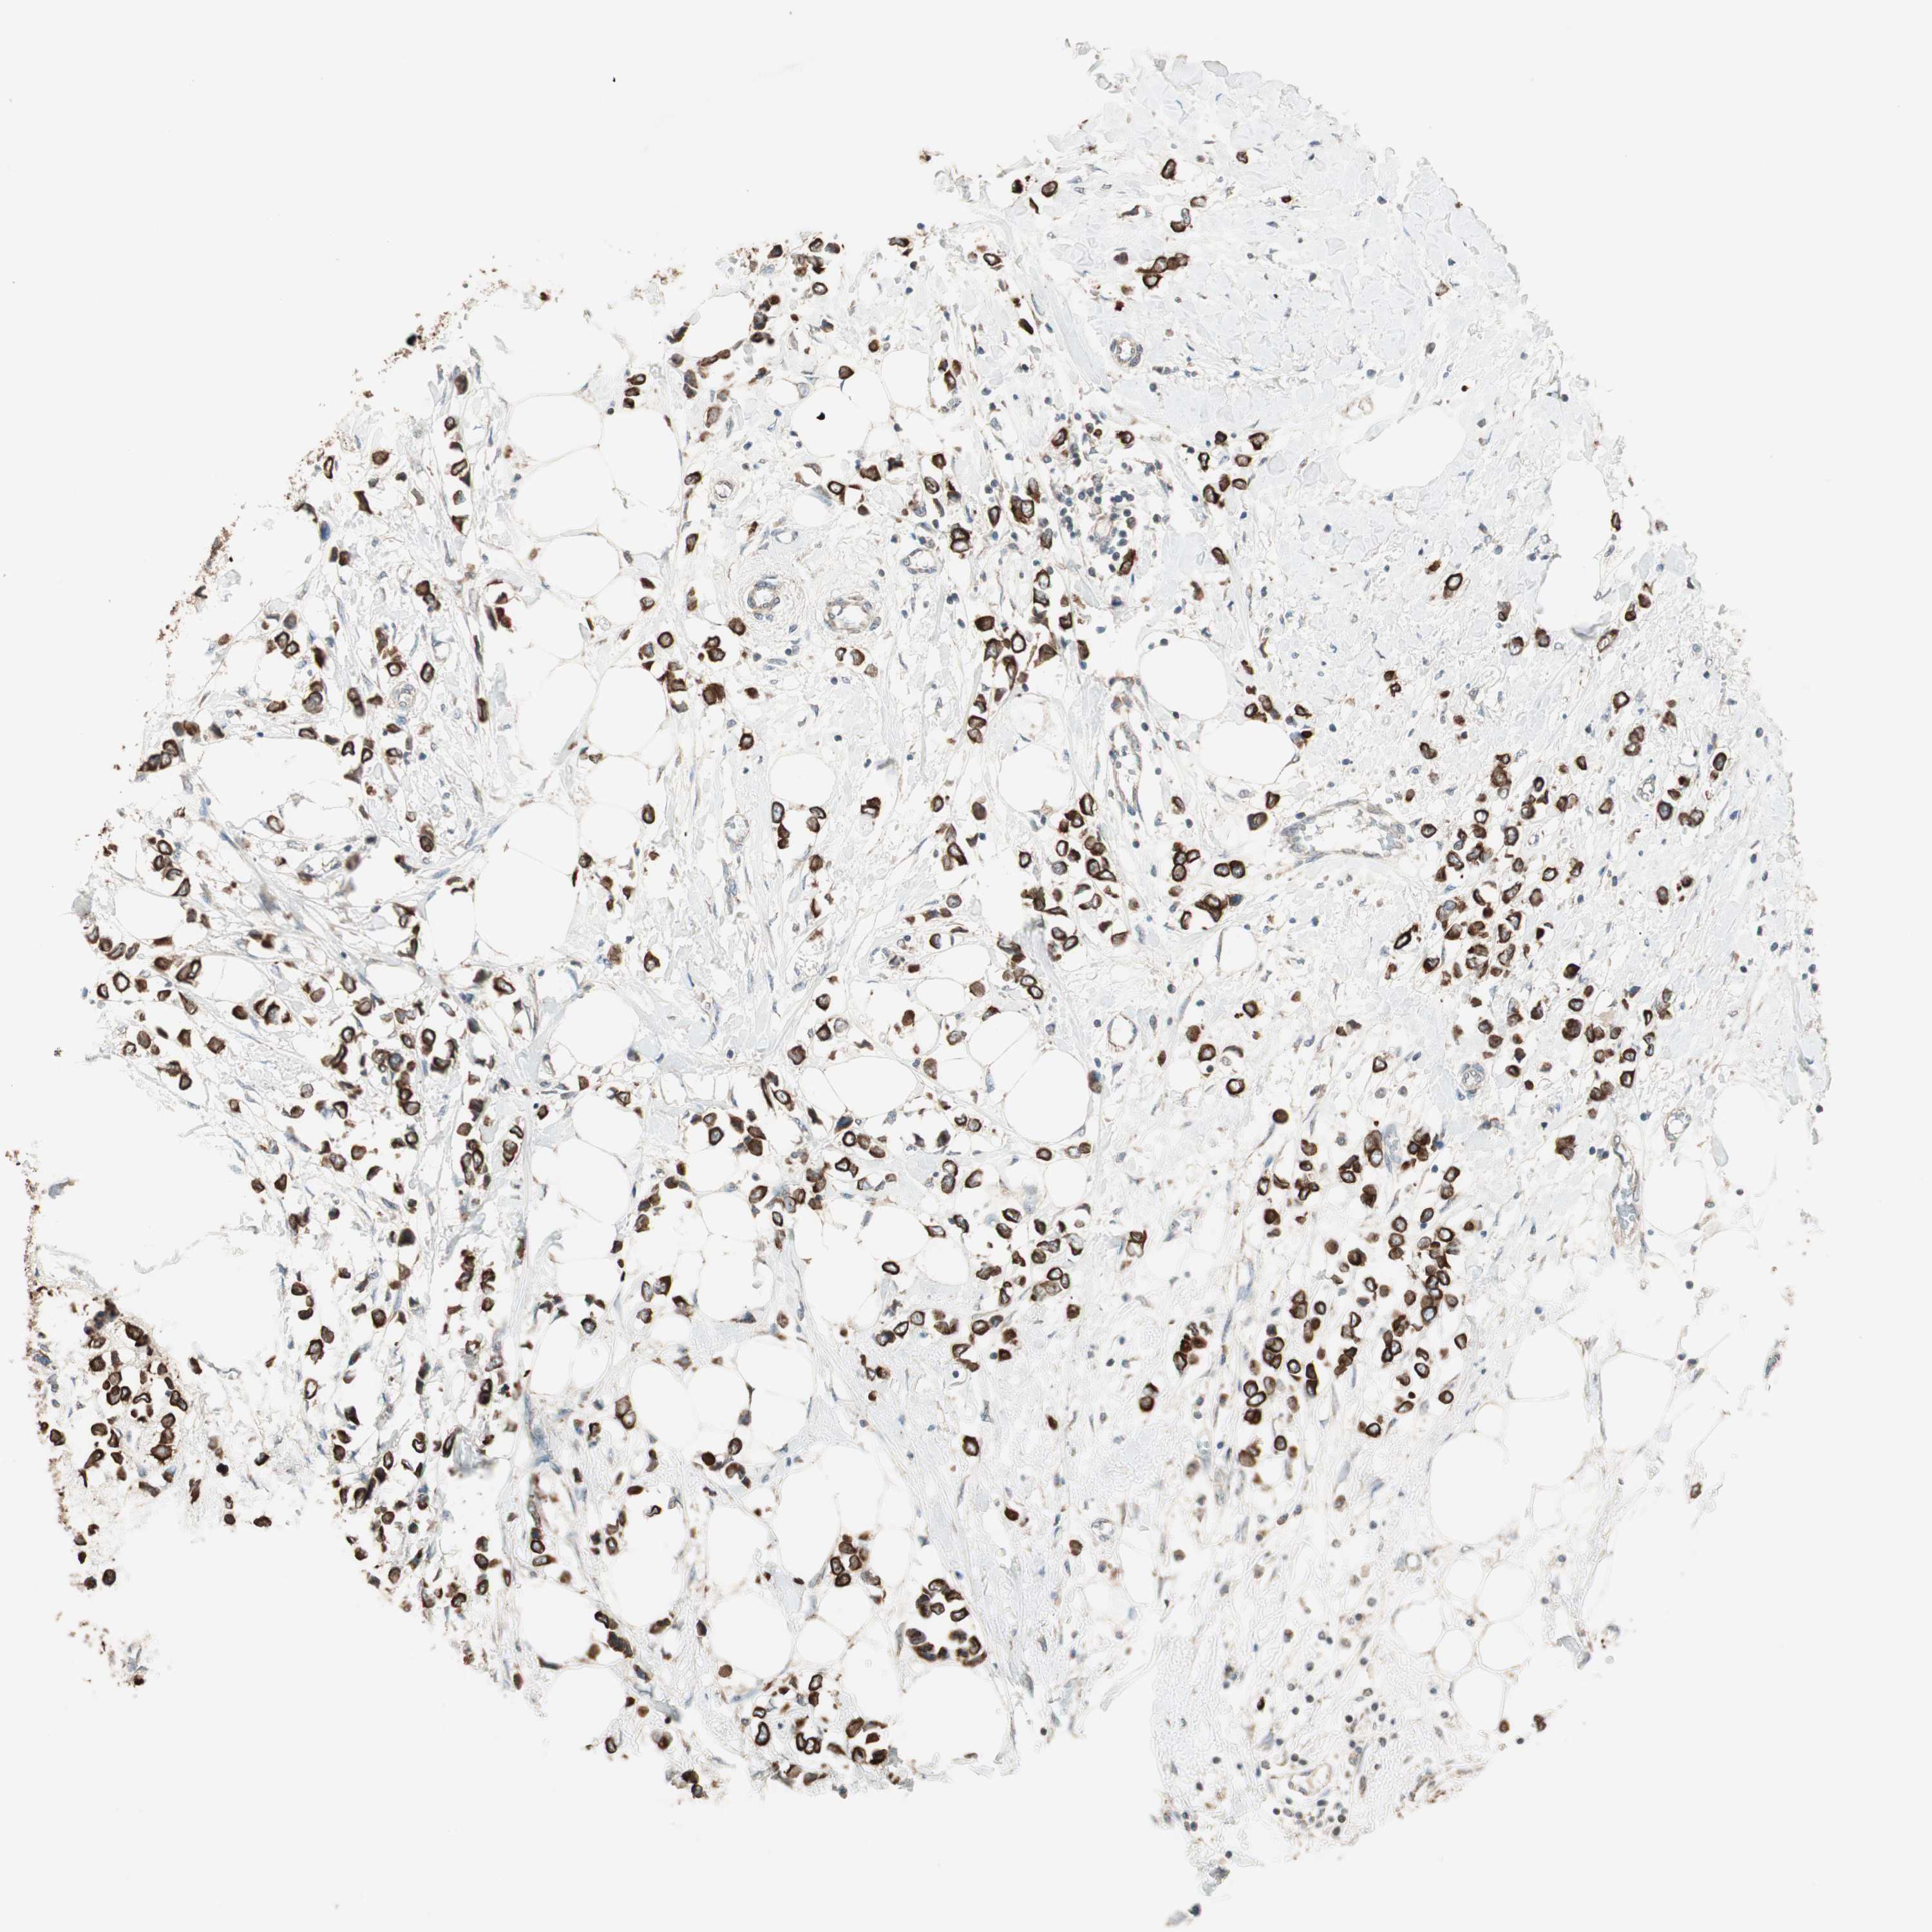

CANCER BREAST CANCER Show tissue menu

BRCA TCGA BRCA VALIDATION PROTEIN EXPRESSION